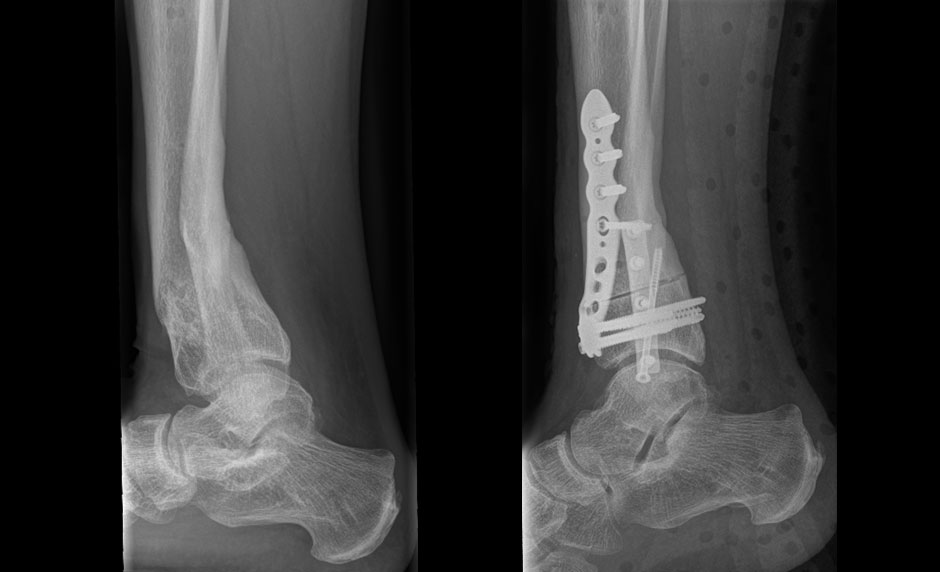

Ventrale closed wedge Umstellungsosteotomie distaler Unterschenkel. A.H. 48, In Rekurvation fehlverheilte distale Unterschenkelfraktur nach multiplen Voroperationen anatomisch reponiert mit ventraler closing wedge Osteotomie.